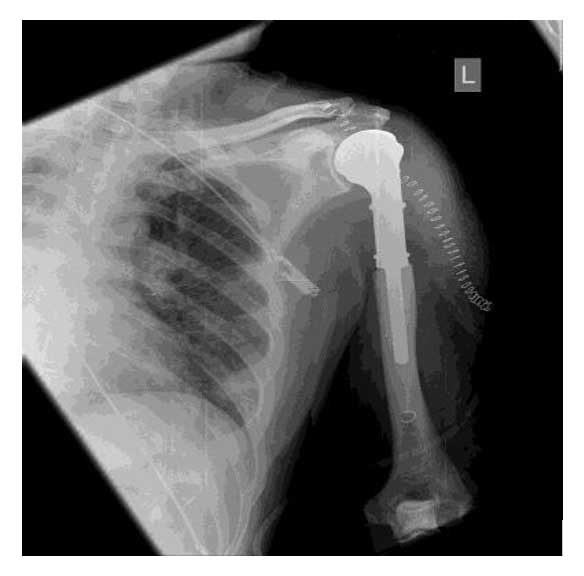

Humerus üst uç metastazına bağlı kırık riski nedeniyle, kemiğin tümörlü bölümü cerrahi olarak çıkarıldı. Eksize edilen alan uygun protez ile yeniden yapılandırılarak kemik bütünlüğü ve kol fonksiyonu sağlandı.

Ameliyat sonrası dönemde herhangi bir komplikasyon gelişmeden hasta taburcu edilmiştir. Ameliyat sonrasında ağrılarında belirgin azalma sağlanmış, kol hareket açıklığı ve günlük fonksiyonlarında anlamlı düzelme gözlenmiştir.

Ameliyat Sonrası: Kemiğin tümörlü kısmının çıkarılıp protez uygulanımı görülmekte.